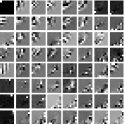

IV-A Transform Learning

To better understand the potential of the MRST model, we vary the number of layers and pre-learn transforms for ST, MRST2, MRST3, MRST5, and MRST7, which possess , , , , and layers, respectively. We used 7 slices of the Mayo Clinic data to train the models. For each model, we run 1000 to 2000 iterations of the learning algorithm to ensure convergence. Fig. 1 shows some of the learned transforms, with each transform matrix row displayed as a square patch for simplicity. The single layer transform displays edge-like and directional structures that sparsify the image. However, with more layers, finer level features are learned to sparsify transform domain residuals in deeper layers. Nonetheless, transforms in deep layers could be more easily contaminated with noise in the training data, since the main image features are successively filtered out over layers.